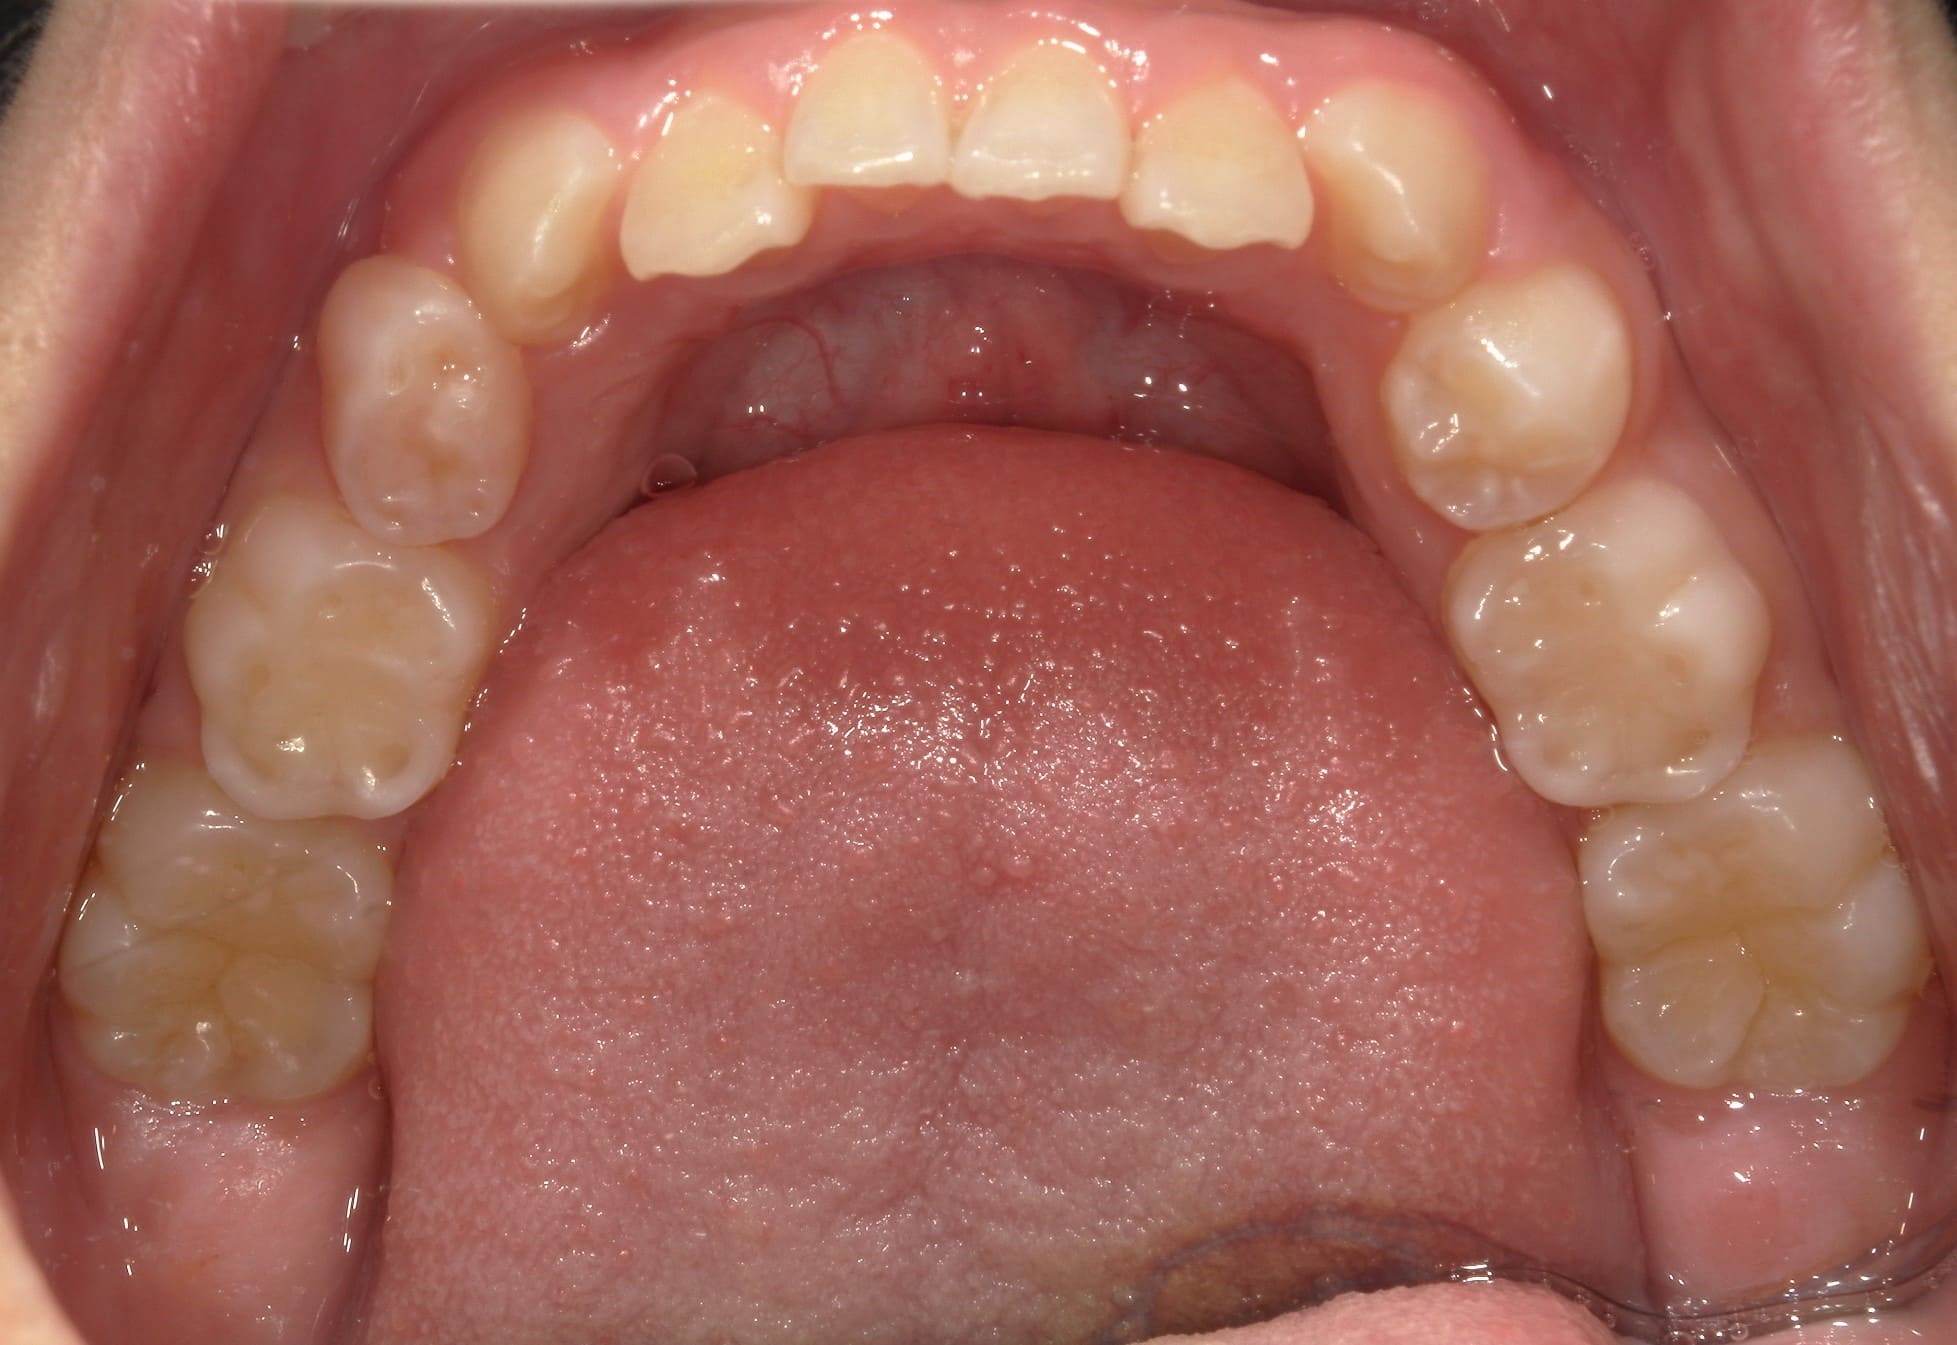

| 年齢・性別 | 8歳9ヶ月の男児 |

|---|---|

| 主訴 | 前歯の咬み合わせが逆になっており、歯根や歯肉への影響を懸念されて来院された患者様です。 |

| 治療期間・回数 | 3年7ヶ月・20回 |

| 費用 | 460,000円(税別) |